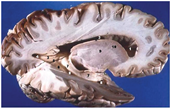

Table 2, Table 3, Table 4 and Table 5 present the results obtained through the multi-objective optimization image enhancement approach. Specifically, Table 2 and Table 3 show the results for natural images, while Table 4 and Table 5 display medical images. The tables are organized as follows: the first and second columns list the image names and their corresponding original, unenhanced versions. The third to fifth columns showcase the selected points from the Pareto front, representing the maximum contrast, knee point, and maximum detail, in that order. The final column illustrates the obtained Pareto front through the optimization process, with red, green, and orange points indicating the images that achieved maximum contrast, knee point, and maximum detail, respectively.

Table 4.

Medical image results—1.

Table 5.

Medical image results—2.

As observed in the results, the images extracted from the Pareto front significantly maximize contrast and detail compared to the original images. In all study cases, the original image is dominated by the solutions extracted from the fronts, demonstrating the approach’s effectiveness in improving visual quality. However, the differences among the three enhanced images for each problem require a more detailed analysis.

For medical images, there are instances where differences are more perceptible. For example, in the Medical3 image, the maximum contrast solution makes it difficult to visualize the internal details of the basophil (a white blood cell highlighted in the box), which could result in a less accurate interpretation. In contrast, the knee and maximum detail solutions provide a clearer view of the interior of the white blood cell. Similarly, in the Medical5 image, the maximum contrast solution highlights the hand and arm bone structures. However, the maximum detail image offers a more precise view of the internal structures within the bones (see the highlighted region), which is crucial for a more detailed evaluation. Another notable example is the Medical8 image, where the maximum detail solution offers a more detailed view of the internal structure of the eosinophil (another type of white blood cell). However, the maximum contrast image improves the visibility of red blood cells. As shown in the yellow box, this solution reveals a red blood cell that is nearly imperceptible in the other solutions. An interesting case is the Medical6 image, where only a few non-dominated solutions are present on the Pareto front. Despite the similarities among the preferred solutions, the nodules are much more perceptible in the enhanced images than in the original image, as observed in the highlighted region.